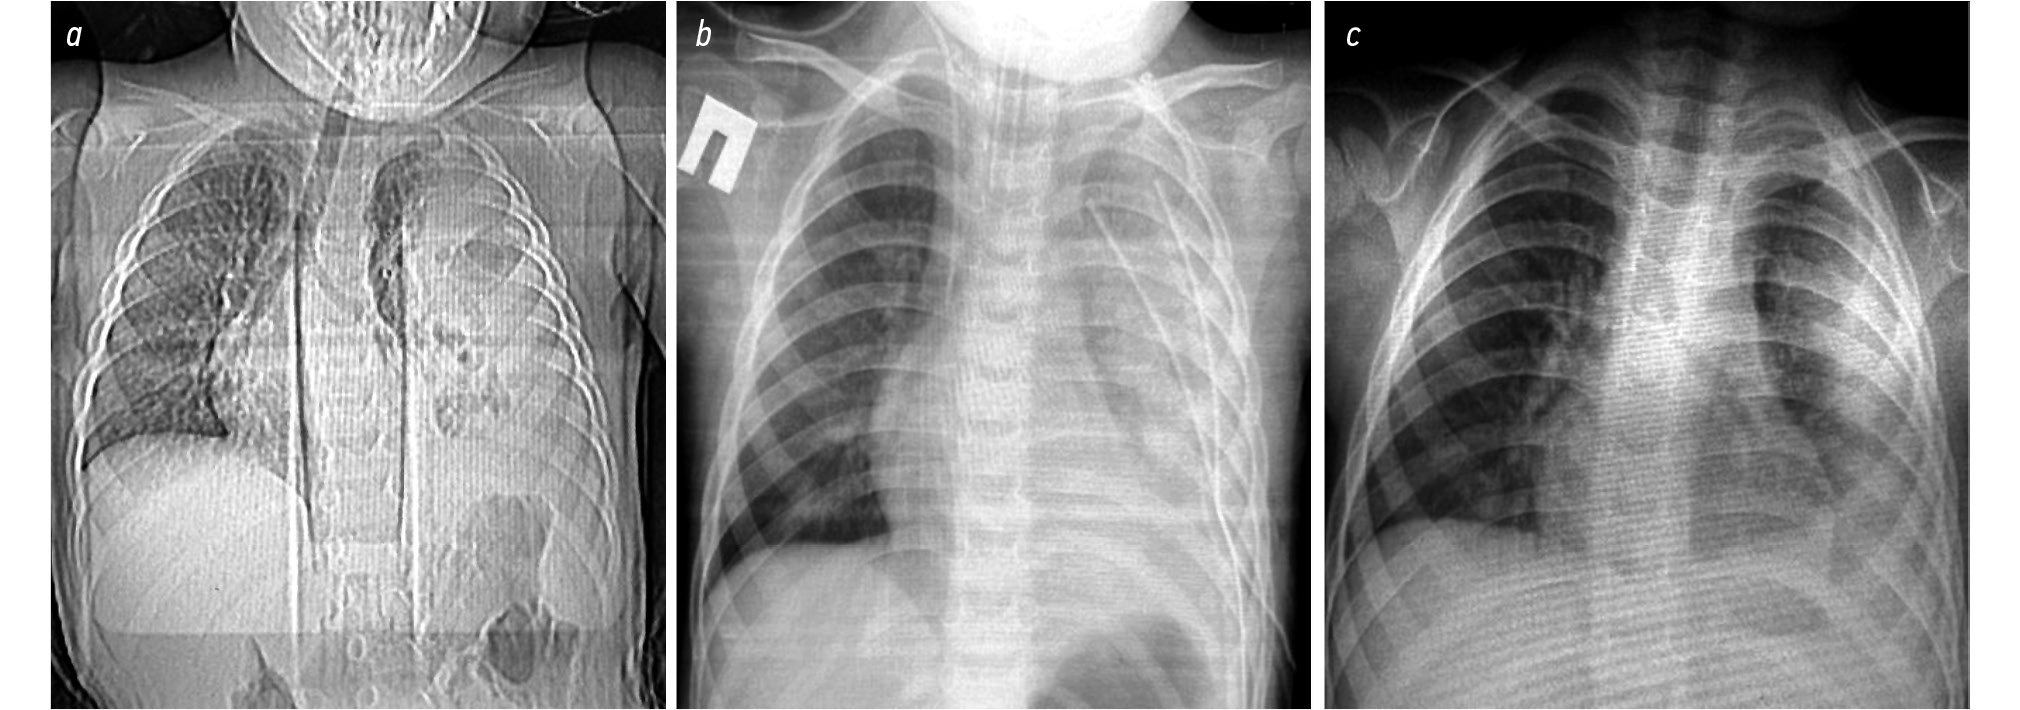

Пациентам основной группы после кавитации УЗНЧ последовательно вводили аспиратор-ирригатор через рабочие торакопорты и орошали плевральную полость и лёгкие раствором препарата «Химопсин» (ООО «Самсон-Мед», Россия) — 0,01 мг лиофилизата в 0,2–0,5 л. изотонического раствора натрия хлорида; экспозиция 10 мин (Способ лечения ОЭП у детей, Патент RU2770663). Затем аспирировали раствор и отделившиеся фибриновые массы, под визуальным контролем промывали плевральную полость изотоническим раствором натрия хлорида (рис. 2). Контрольную рентгенограмму грудной клетки проводили в 1-е сут после операции. На 2-е сут после операции через плевральные дренажи орошали плевральную полость 0,1–0,2 л. раствора препарата «Проурокиназа» (ООО НПП «Техноген», Россия) в концентрации 5000 МЕ при температуре 36,6°С; экспозиция раствора 180 мин. Затем аспирировали содержимое плевральной полости шприцем и промывали плевральную полость 1,0 л изотонического раствора натрия хлорида. У всех детей использовалась активная аспирация.

Рис. 2. Интраоперационная картина эффективности применения препарата «Химопсин».

Fig. 2. Intraoperative picture demonstrating Khymopsin effectiveness.